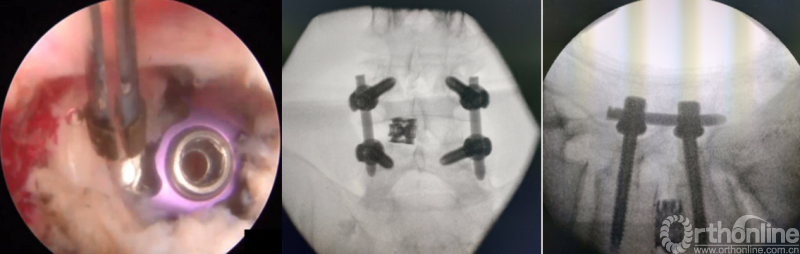

PE-PLIF技术十步法

详细步骤:一定、二辨、三凿、四分、五咬、六切、七旋、八铰、九填、十置

第八步“铰”:盲视下可撑开铰刀置入,撑开并处理上下终板;

第九步“填”;椎间隙填塞植骨;

第十步“置”:置入融合器、经皮钉。